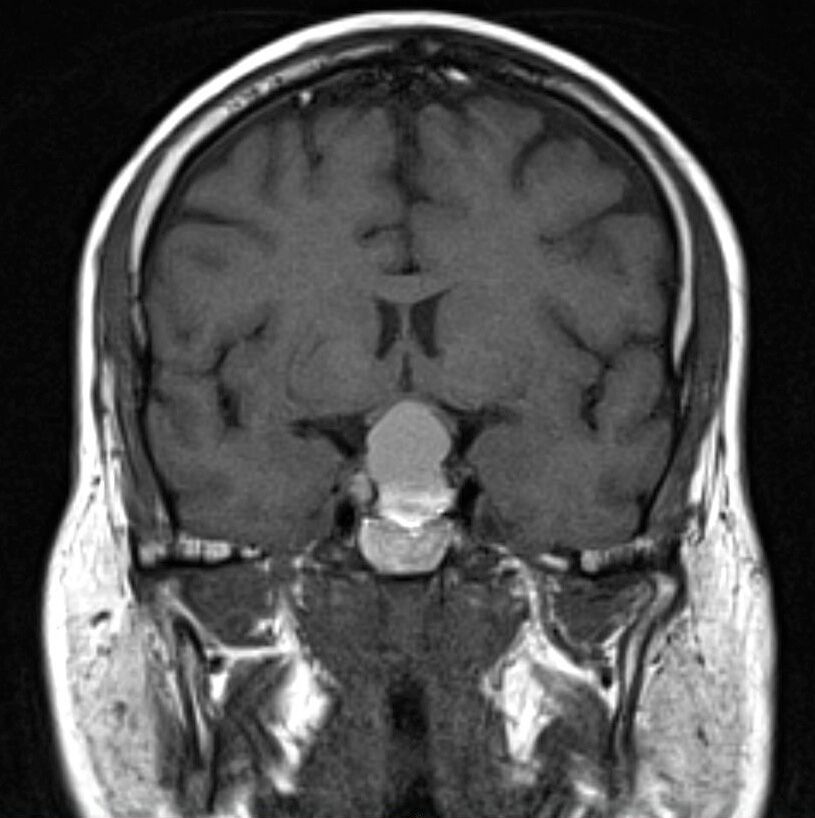

Brain Tumor MRI Classification

Deep learning model for automatic classification of brain tumors from MRI scans. Fine-tuned ResNet-50 to distinguish glioma, meningioma, pituitary tumor, and no tumor. Achieved 99.2% test accuracy using transfer learning, data augmentation, and robust evaluation.

- Transfer learning with ResNet-50; custom head for 4-class classification.

- Data augmentation: flips, rotations, color jitter for generalization.

- Comprehensive metrics: precision, recall, F1-score, confusion matrix.

Medical Imaging

Deep Learning

ResNet-50

PyTorch